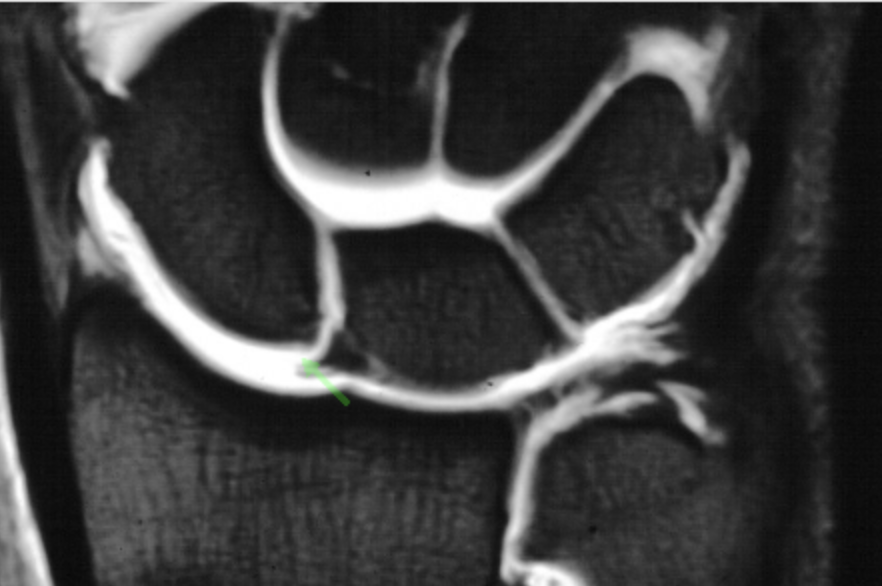

腕部远端桡尺关节测试

腕部 DRUJ 球拍测试远侧桡尺关节球拍测试的可靠性和有效性分析 Nagashima, M., Omokawa, S., Hasegawa, H., Nakanishi, Y., Kawamura, ...